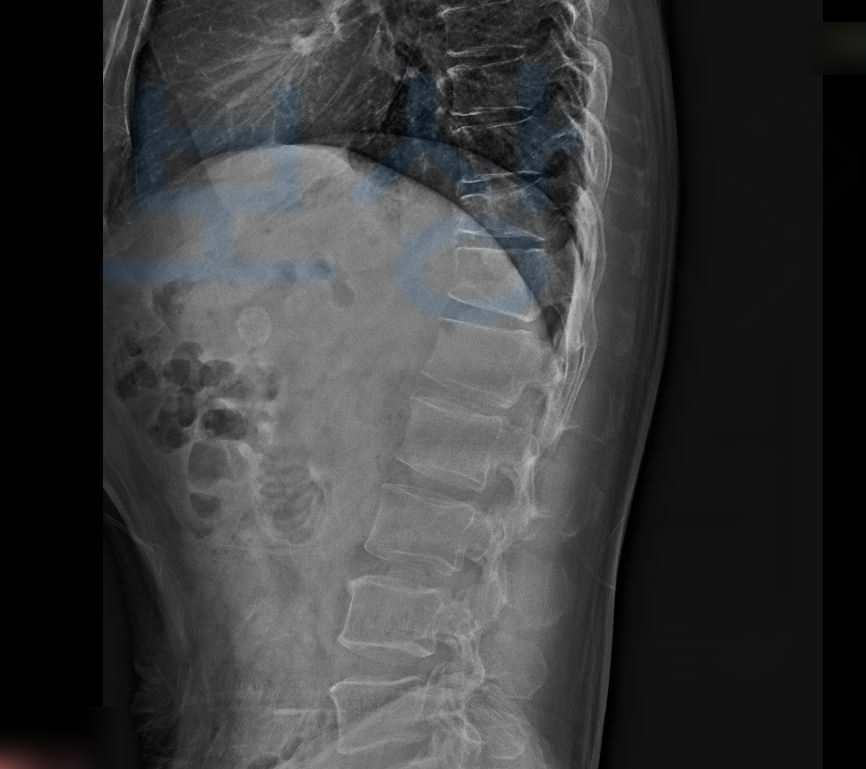

흉추11번, 흉추12번 골절

권@@님은 척추보조기 (TLSO)를 착용하시며 전치8주 즉 8주간의 안정을 취하셔야 했습니다. 권@@님은 사고 초기부터 보상파트너에 연락주셔서 함께 보험증권과 사고경위, 영상CD를 보고 상담을 도와드렸습니다.

뿐만 아니라 허리 골절, 즉 흉추 골절은 골절진단비,실비,입원비 뿐만 아니라 후유장해보험금도 확인하셔야 합니다. 저희는 보상 가능성을 확인해

척추의 뚜렷한 기형을 남긴 때 30%의 지급률을 모두 인정받게 되어 1억의 30% ,3,000만원의 보상 받으셨습니다. 권@@님의 경우 교통사고 전치8주 합의금과 개인보험의 장해 보상으로 총 6,500만원의 보상 받으신거죠.